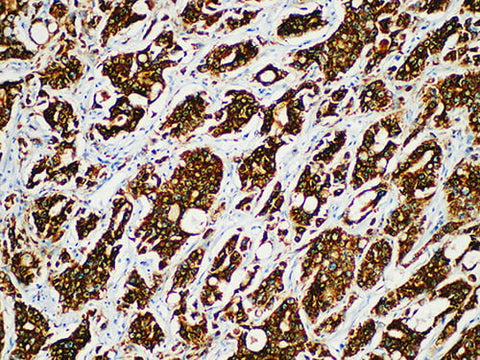

AMACR/p504s Monoclonal Antibody Synonyms AMACR/p504s

Applications IHC-P

Tissue Specificity Prostate cancer

Alpha-methylacyl-CoA racemase (AMACR), also known as P504S, is a mitochondrial and peroxisome enzyme. AMACR is expressed in normal liver (hepatocyte), kidney (tubular epithelial cell) and gallbladder (epithelial cell). AMACR is also expressed in Lung (bronchial epithelial cells) and colon (surface epithelium of colon). AMACR is a specific marker of prostate cancer.